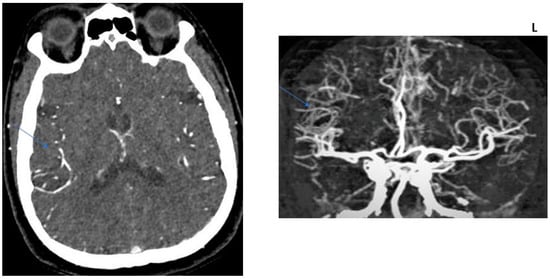

2.2. CT Protocol